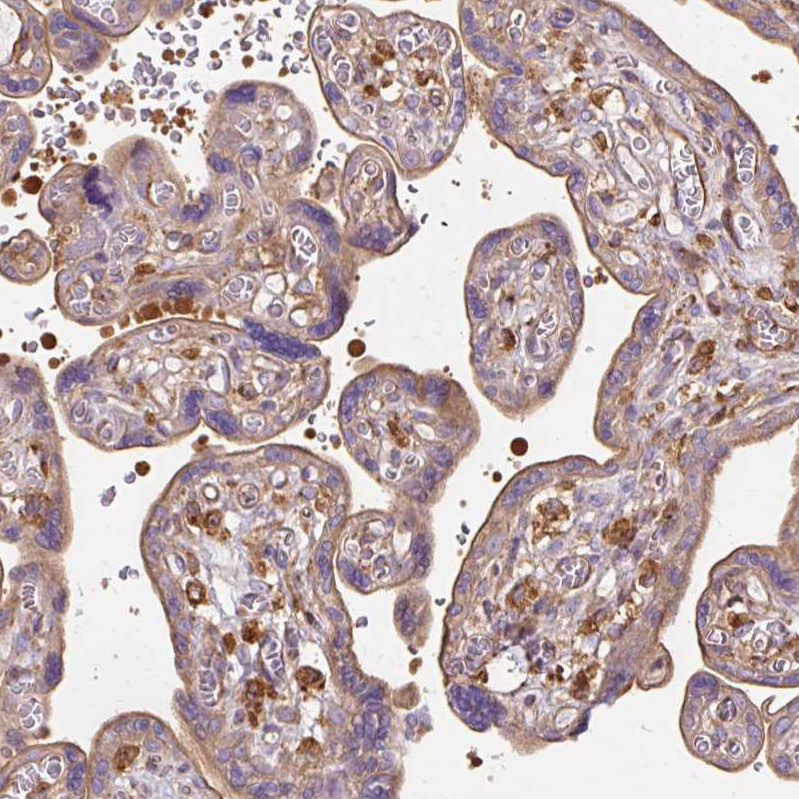

Immunohistochemical staining of human placenta shows moderate cytoplasmic and membranous positivity in trophoblastic cells.